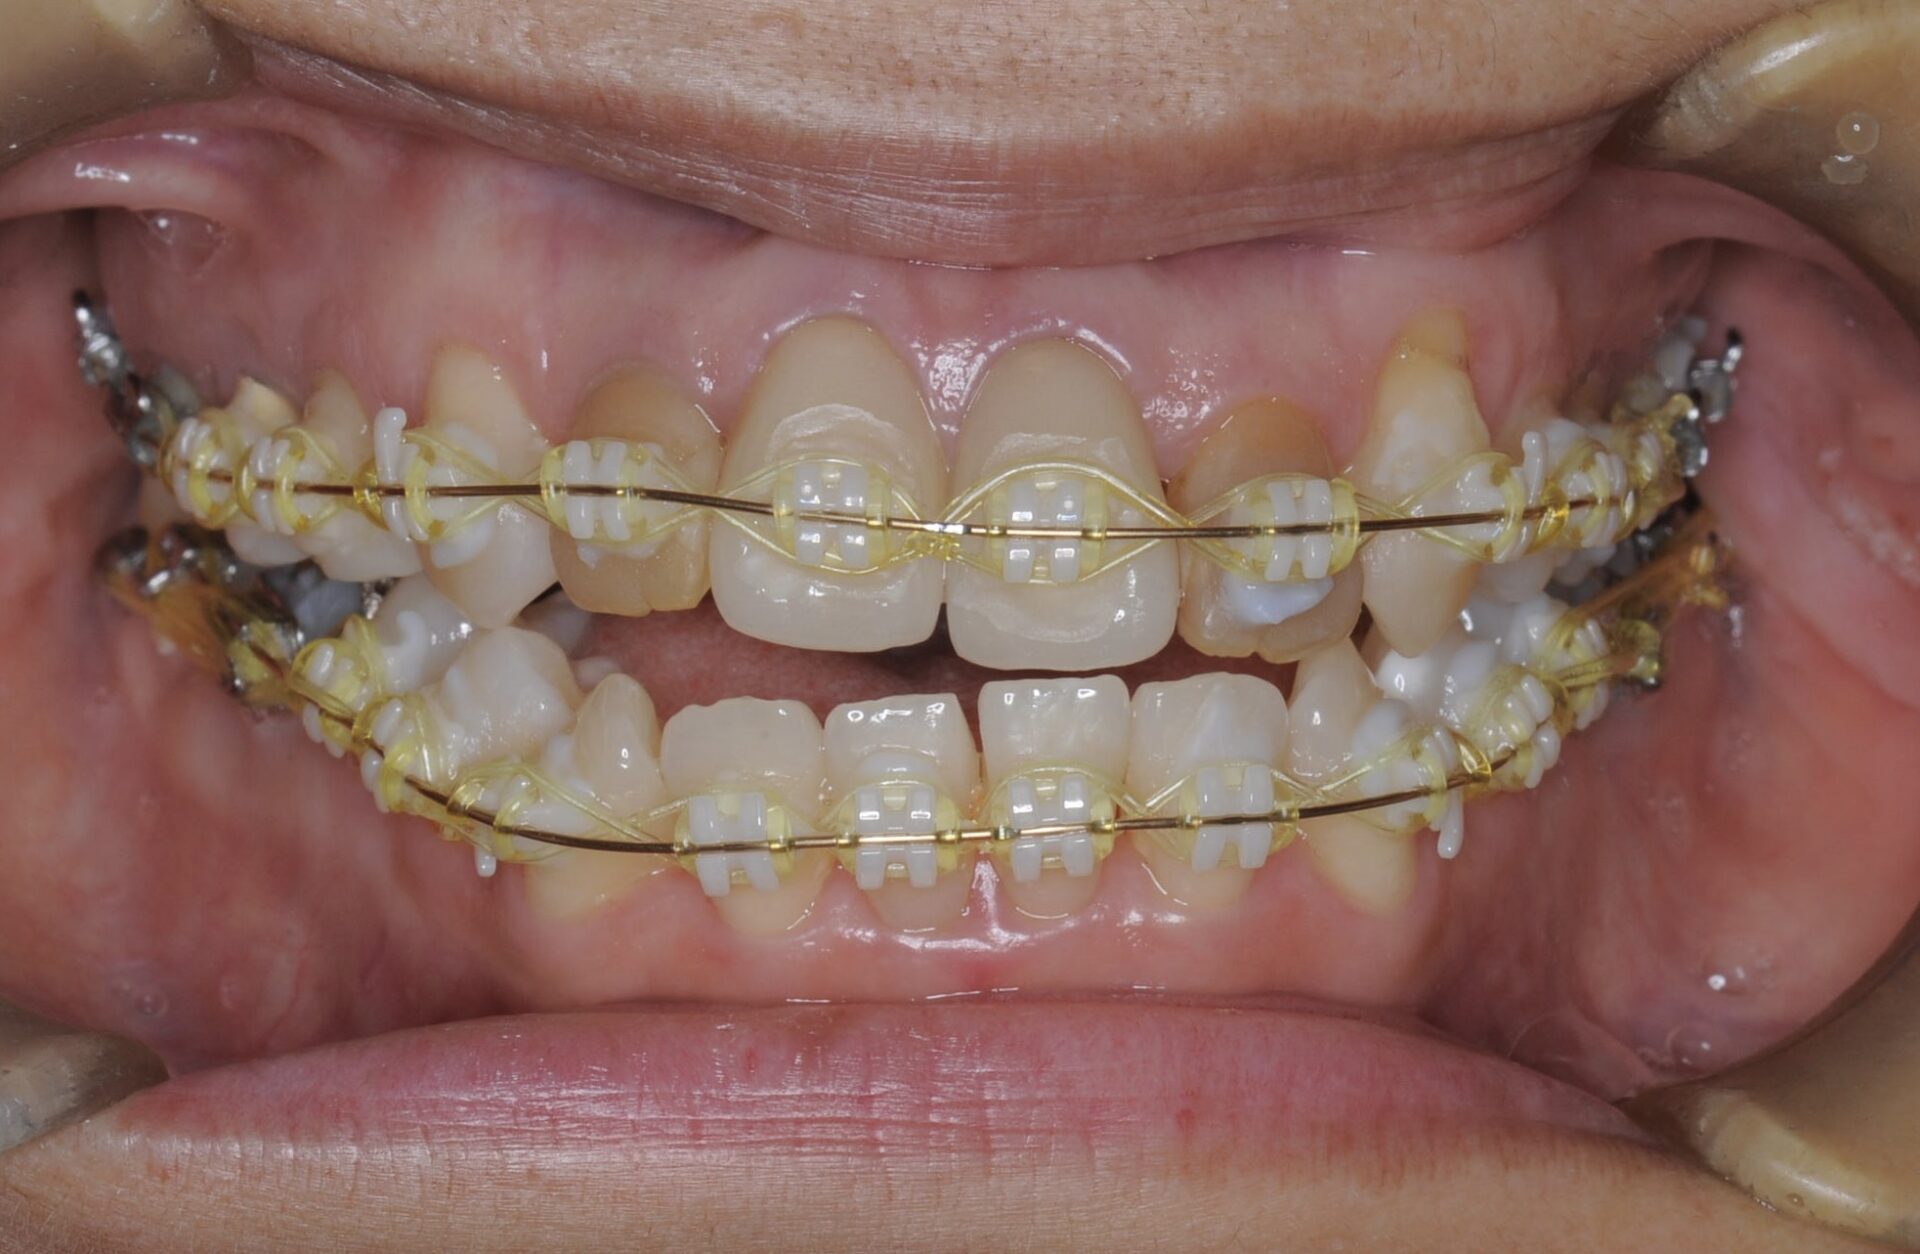

矯正中

左側は噛んできたが、右側は逆の動き、つまり右側中切歯が上に上がっていってしまっている。側切歯のアンキローシス(骨癒着)を疑う。

2週間ほど側切歯の上側にワイヤーを通し周りの歯の動きを見ていると、通常であれば側切歯が下がるはずが側切歯はそのままの位置で、中切歯がより上に動いていた。よって側切歯のアンキローシストと診断する。

側切歯のブラケットを外し力をかけないようにしていると、中切歯は周りの歯に合わせて下に降りてきた。